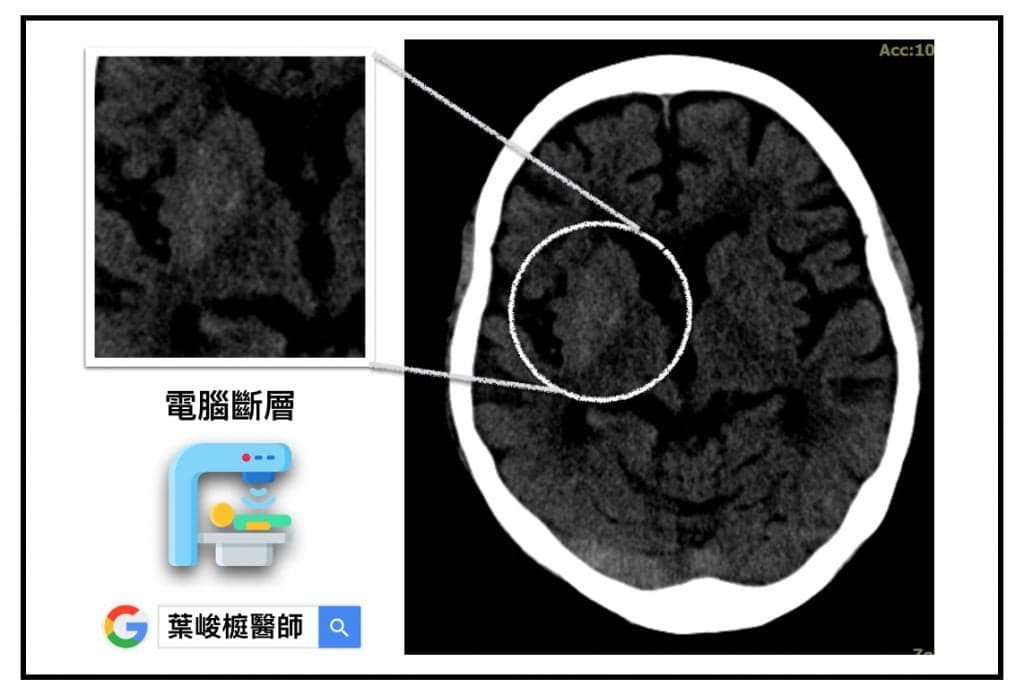

非酮性高血糖症致單側舞蹈症, 電腦斷層

突發性單側舞蹈症❓竟然是高血糖在作怪❗️